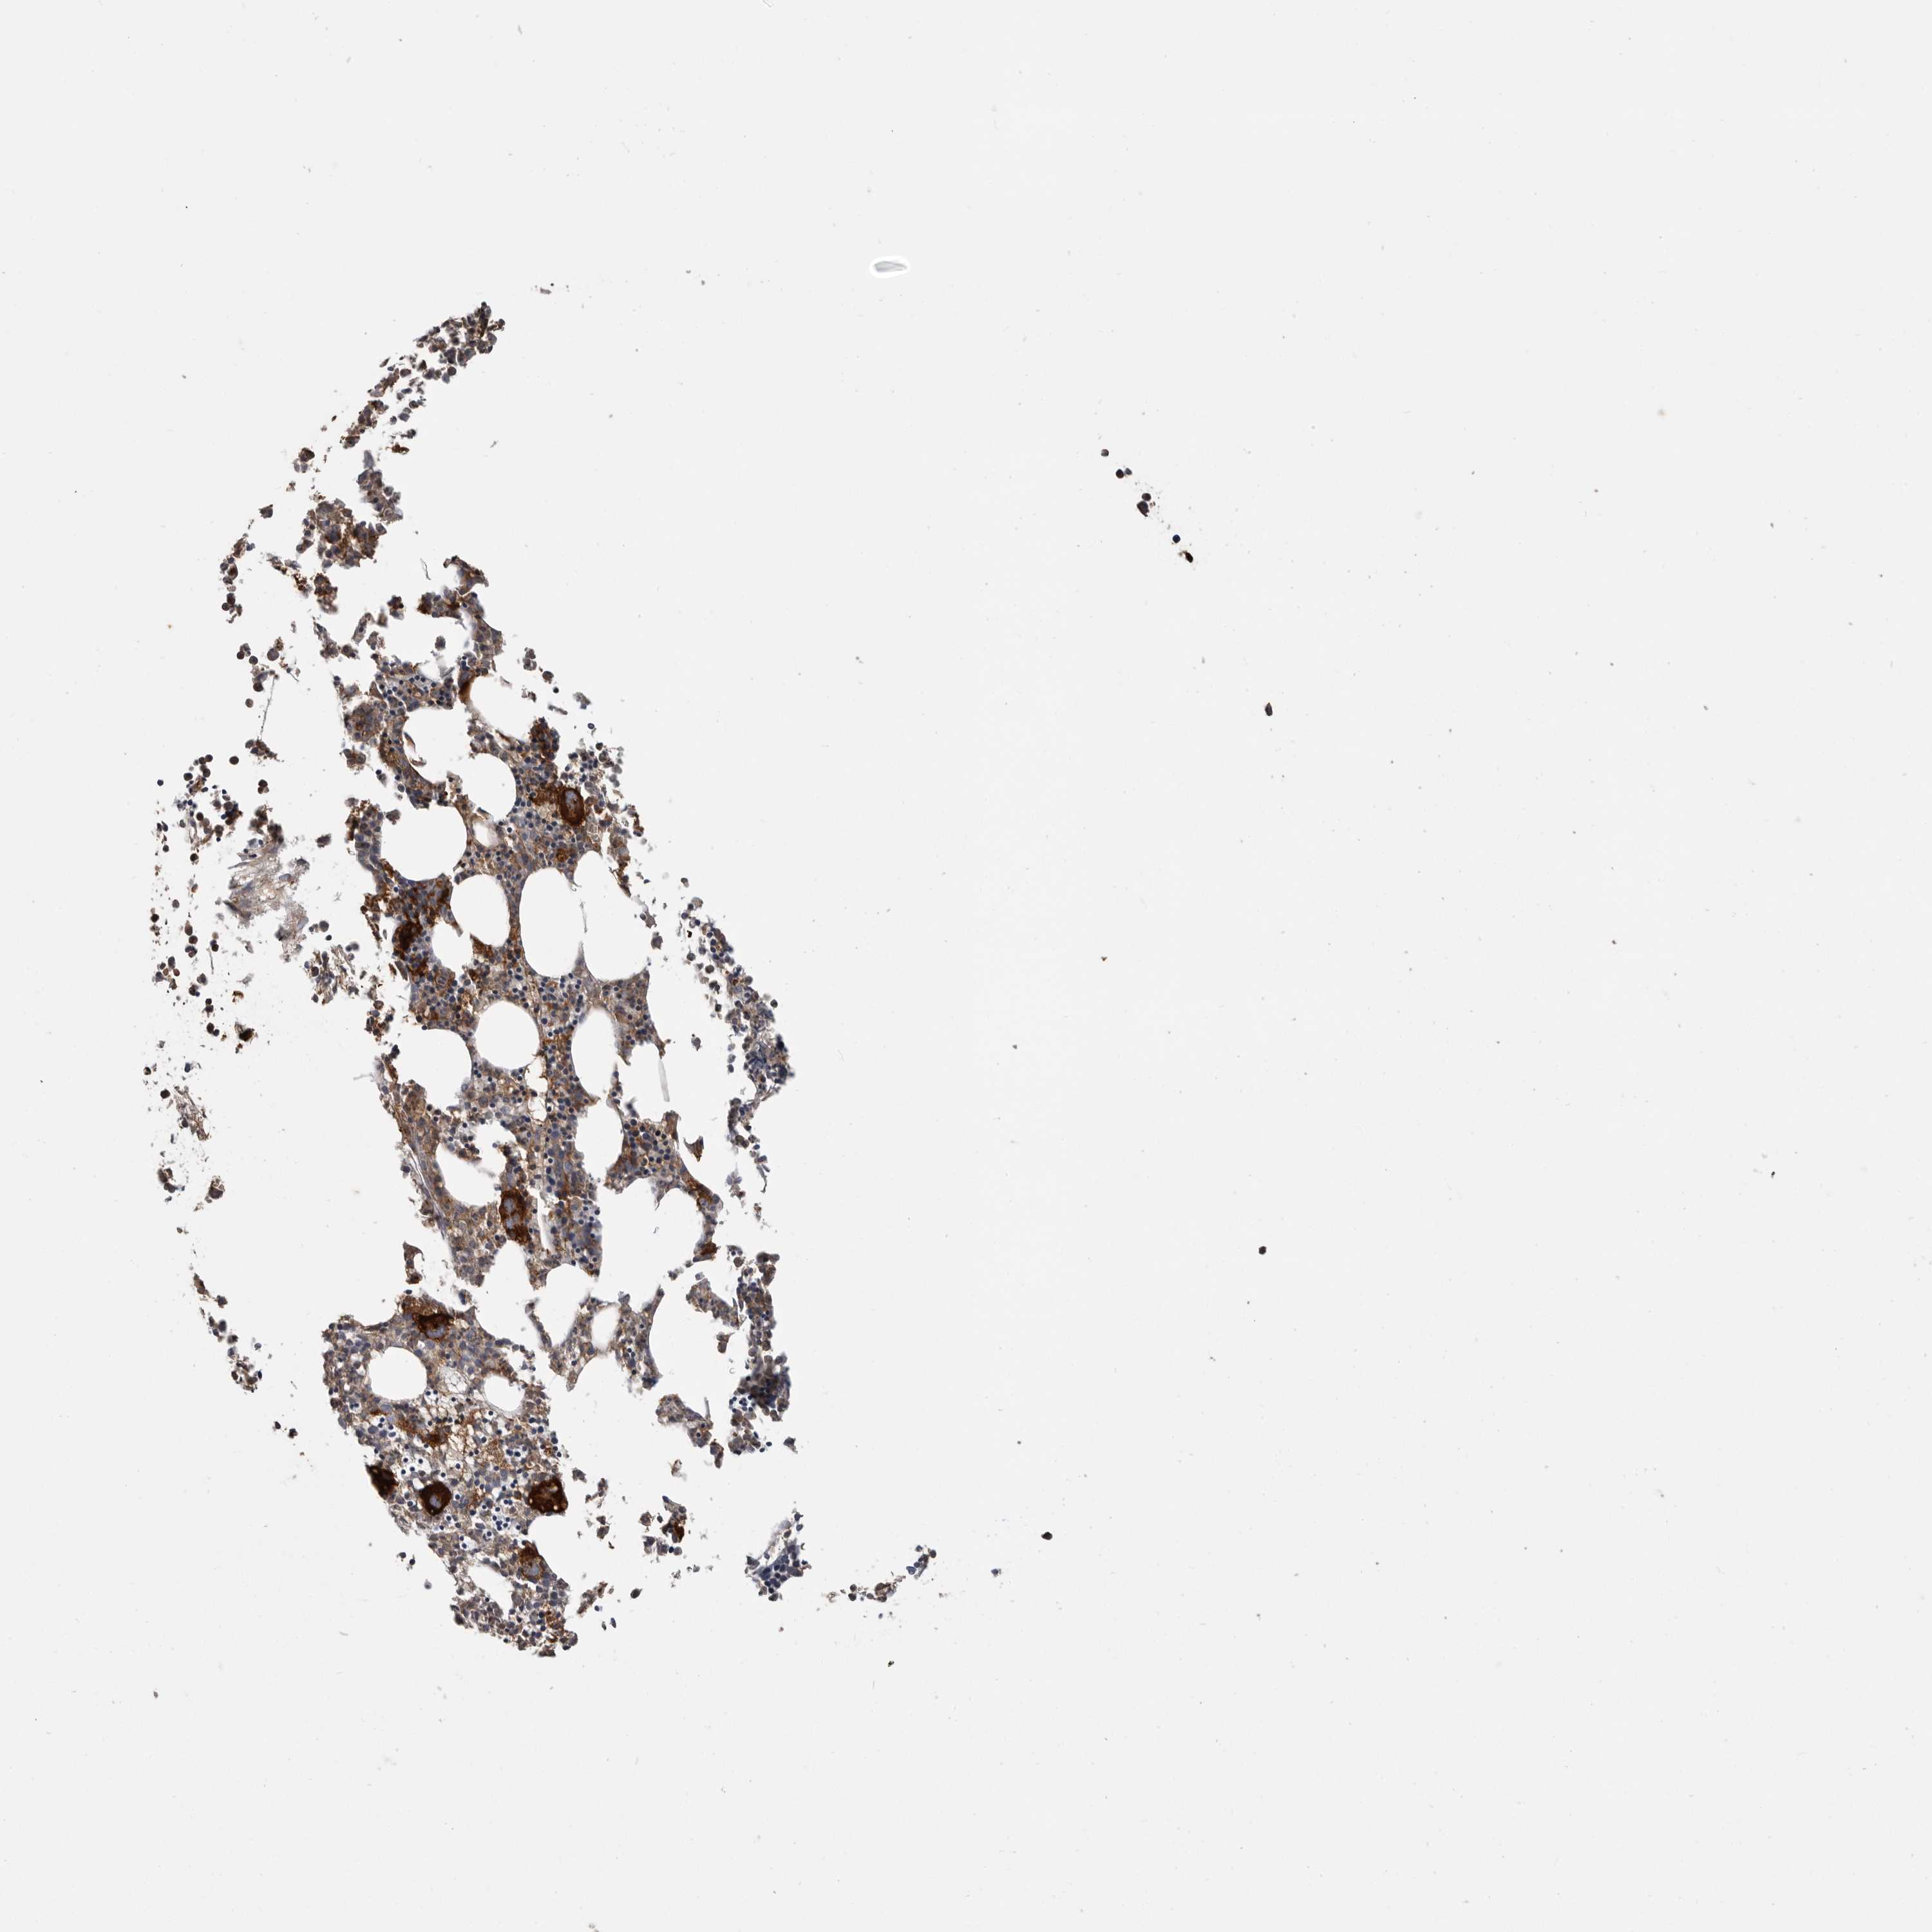

BONE MARROW - Antibody stainingi

Antibody staining in the annotated cell types in the current human tissue is reported as not detected, low, medium, or high, based on conventional immunohistochemistry profiling in selected tissues. This score is based on the combination of the staining intensity and fraction of stained cells. Each image is clickable and will lead to virtual microscopy that enables deeper exploration of all samples and also displays staining intensity scores, fraction scores and subcellular localization as well as patient and tissue information for each sample.

Antibody HPA026980

Hematopoietic cells Medium